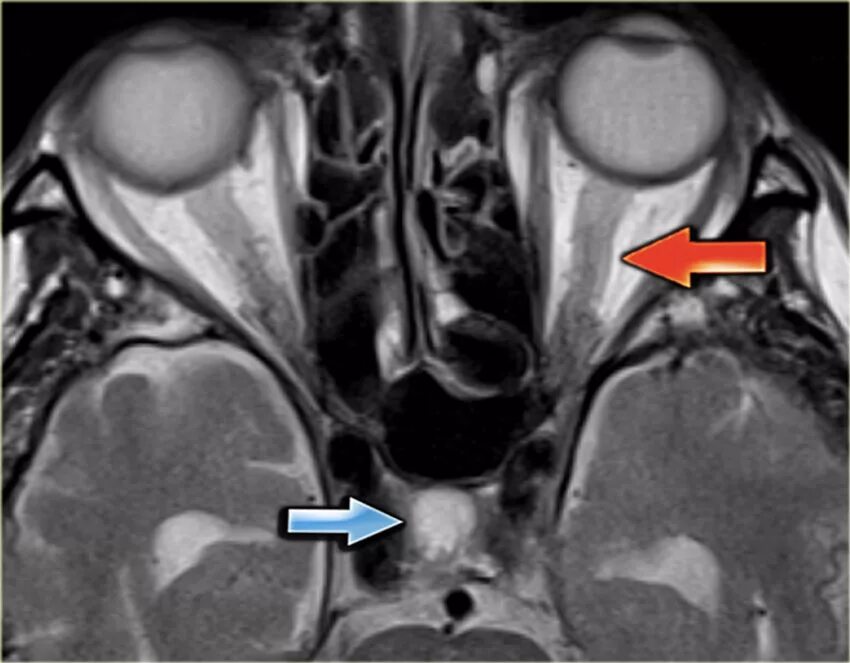

Тромбоз кавернозных